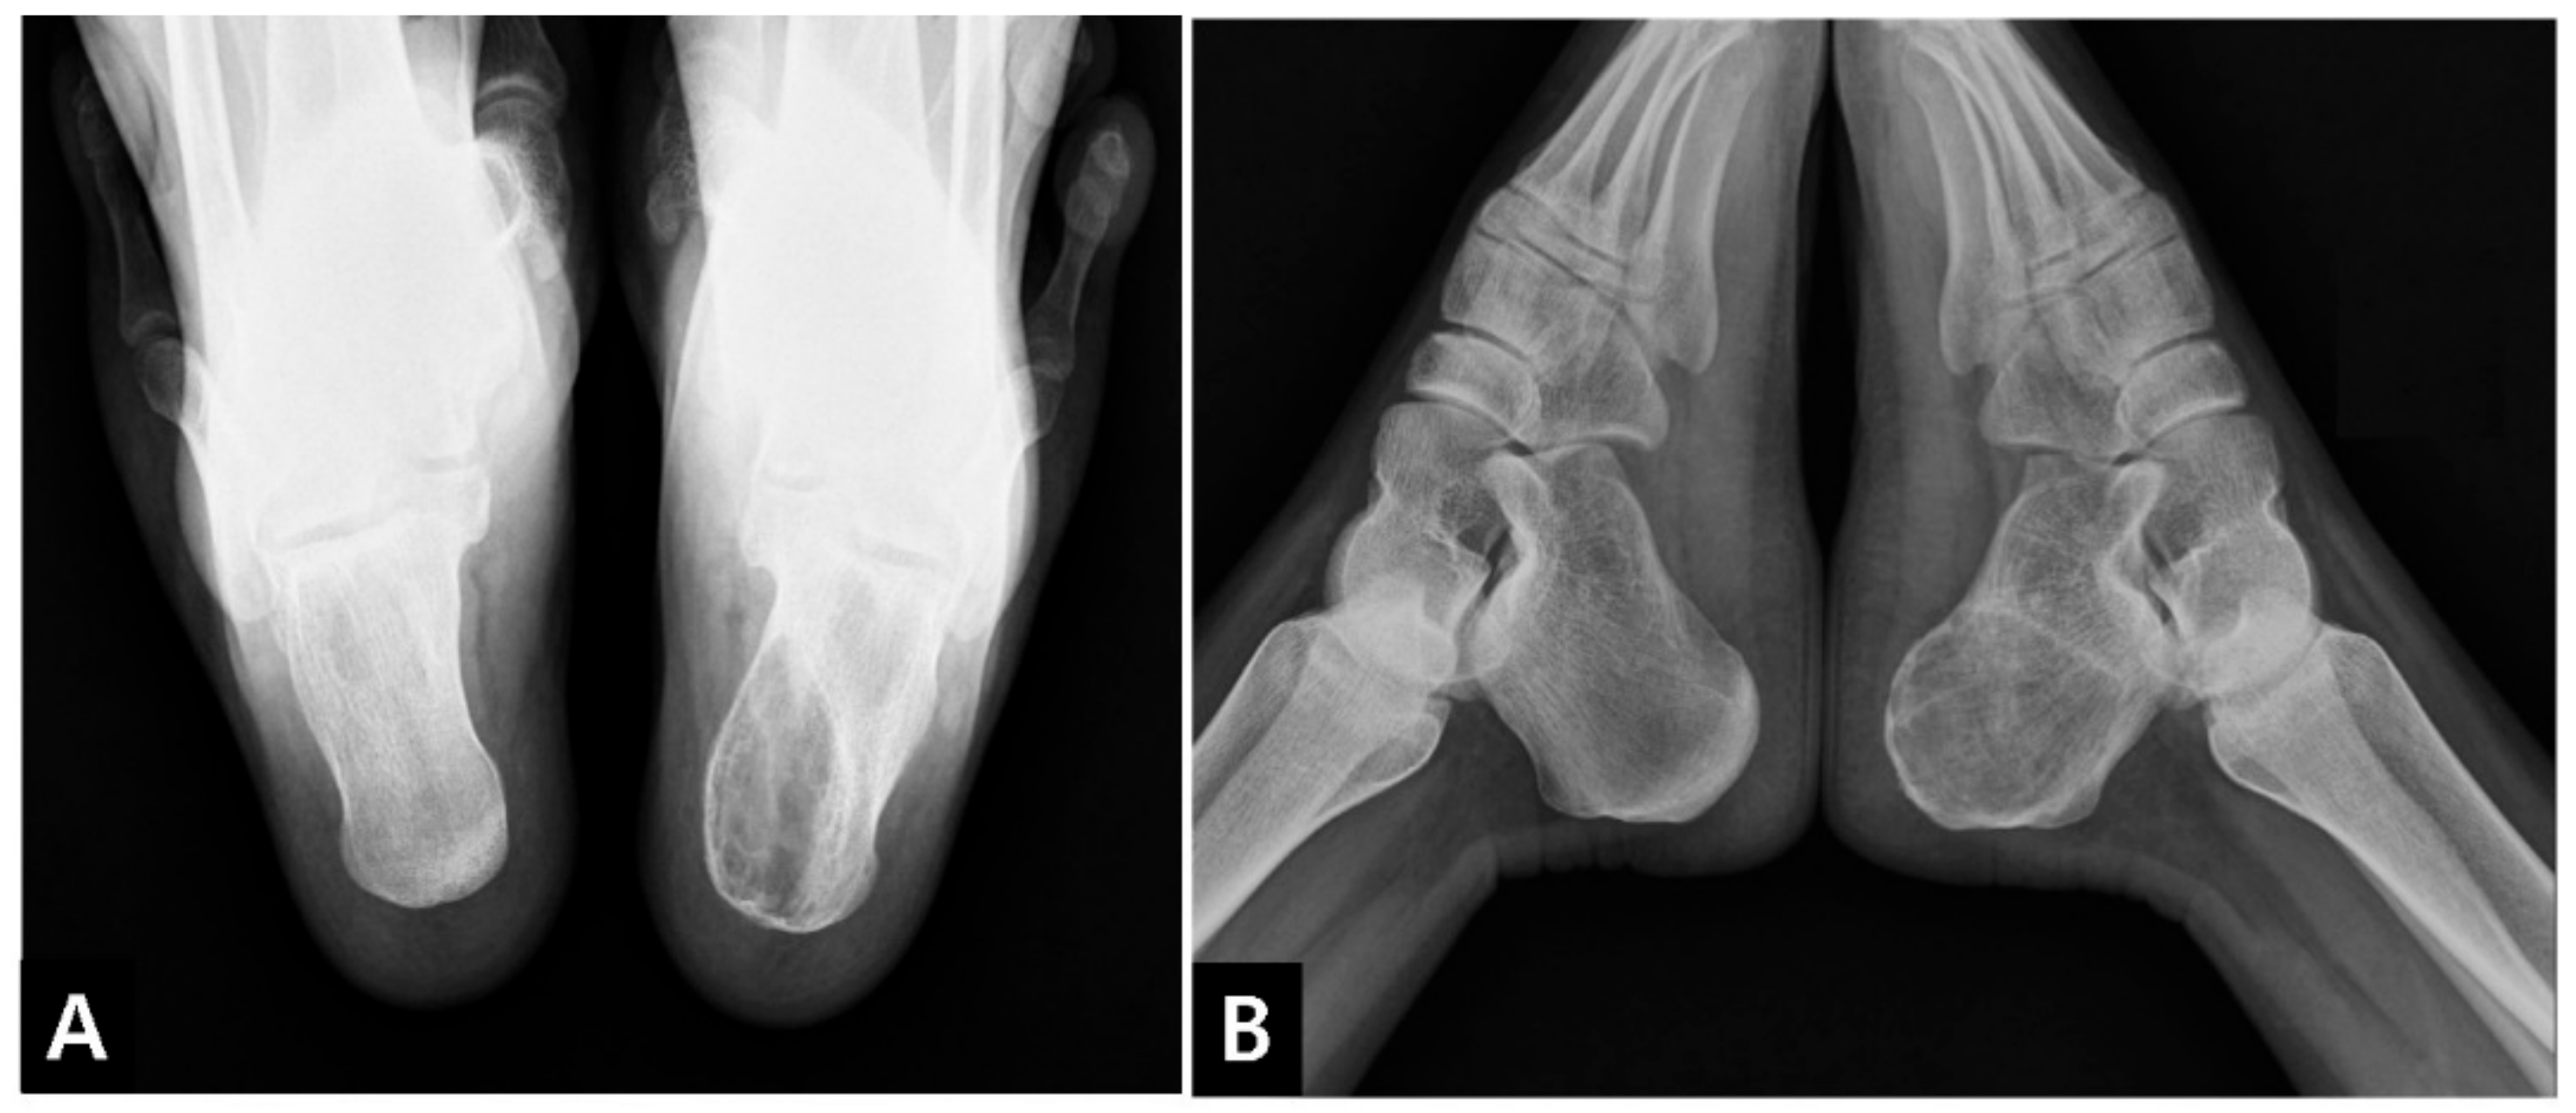

2. Case Presentation

2.3. Postoperative Progression

- Lenze, U.; Stolberg-Stolberg, J.; Pohlig, F.; Lenze, F.; von Eisenhart-Rothe, R.; Rechl, H.; Toepfer, A. Unicameral Bone Cyst in the Calcaneus of Mirror Image Twins. J. Foot Ankle Surg. Off. Publ. Am. Coll. Foot Ankle Surg. 2015, 54, 754–757. [Google Scholar] [CrossRef]